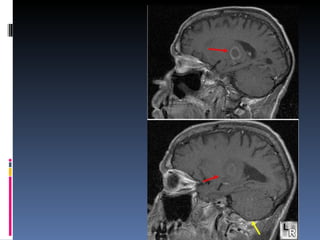

Vraag 107 De thalamus wordt gevasculariseerd door de arteria cerebri media Onjuist

Rood: medial lenticulostriate arteries, branches of A1  ( anterior inferior parts of the basal nuclei and the anterior limb of the internal capsule)

Oranje: lateral lenticulostriate arteries, branches of M1 (superior part of the head and the body of the caudate nucleus, most of the globus pallidus and putamen and the posterior limb of the internal capsule.

Groen: Posterior thalamoperforating arteries branch off the P1 segment and supply blood to the midbrain and thalamus.